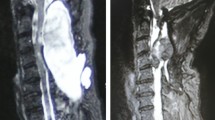

A 70-year-old man presented 1 month after decompressive surgery for lumbar canal stenosis with leakage of cerebrospinal fluid (CSF) from the wound site and severe headache. There were no signs of surgical site infection or meningitis. There was no intraoperative or immediate postoperative evidence of dural tear. He was neurologically intact. On detailed work-up, he was found to have air collections in the subarachnoid and intraventricular spaces in the brain and intraspinal air in both the cervical and the lumbar regions. He showed gradual resolution of these findings radiologically and symptomatic improvement through conservative management with analgesics, empirical antibiotics, high flow oxygen, and maintenance of hydration within 1 month.